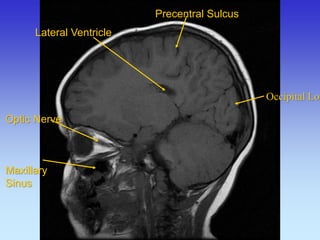

Precentral Sulcus

Lateral Ventricle

Occipital Lobe

Frontal

Lobe

Maxillary

Sinus

Parietal Lobe Occipital Lobe